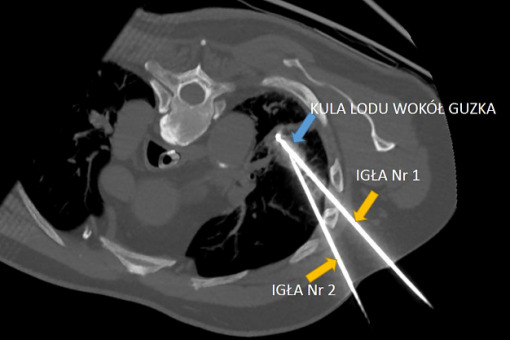

Zespół radiologów interwencyjnych z II Zakładu Radiologii UCK WUM przeprowadził pierwszy w naszym kraju zabieg krioablacji nowotworu płuca. W Polsce opóźnienie w zakresie dostępności radiologii interwencyjnej dla pacjentów onkologicznych sięga 15–20 lat w porównaniu z państwami zachodnimi.